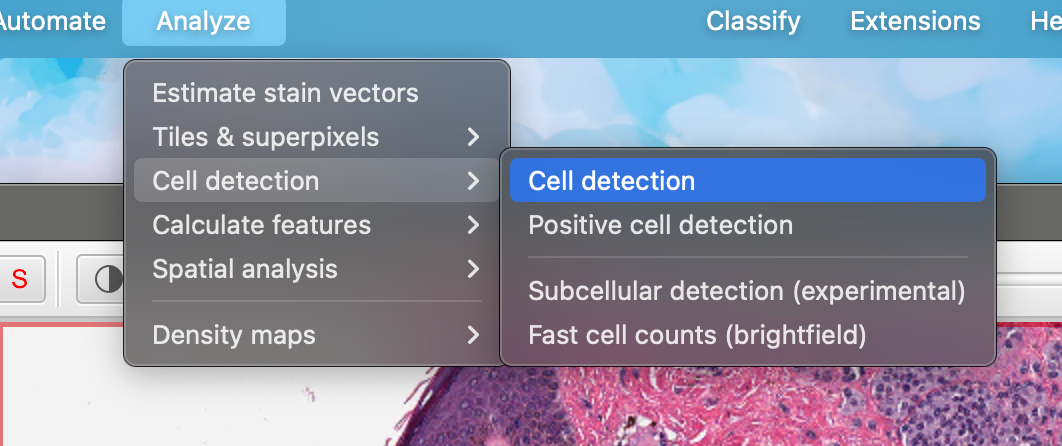

运行“Analyze ‣ Cell detection ‣ Cell detection”命令。

这应该会显示一个令人望而生畏的参数列表,以适应不同图像的检测。

如果您愿意,可以探索这些参数,并在鼠标悬停在每个参数上以获取描述——但现在,您也可以忽略它们并使用默认值(这些默认值通常在各种图像上表现得相当合理)。

点击对话框底部的“运行”按钮。几秒钟后,您所选区域中的细胞应该会出现。这些细胞是您的第一个检测对象。